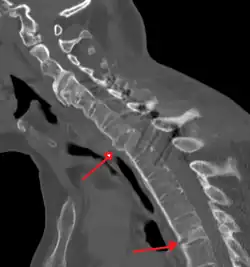

-

Lateral X-ray of the mid back in ankylosing spondylitis -

Lateral X-ray of the neck in ankylosing spondylitis -

X-ray showing bamboo spine in a person with ankylosing spondylitis -

CT scan showing bamboo spine in ankylosing spondylitis -